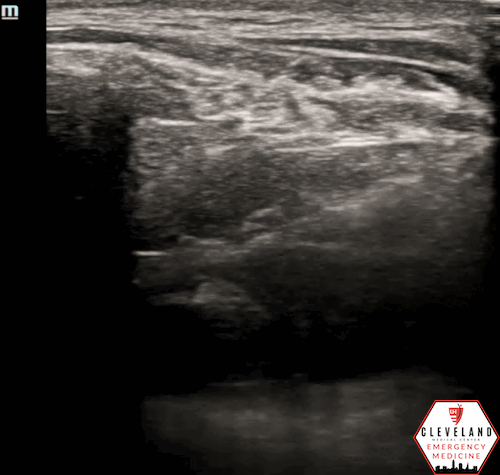

Figure 3. Apical approach - Figure 1. Subxiphoid approach - Source: NUEM Blog — Pericardiocentesis (nuemblog.com)

Apical

• Probe Placement: 4th-5th intercostal space, under the left breast or inframammary fold, near mid-axillary line.

• Probe Orientation: Indicator toward left axilla.

• Needle: Insert in-plane at ~45°, advancing toward the pericardial space.

• Pros/Cons: Similar to parasternal approach in advantages; the short distance from chest wall allows improved visualization and safety [4,5].